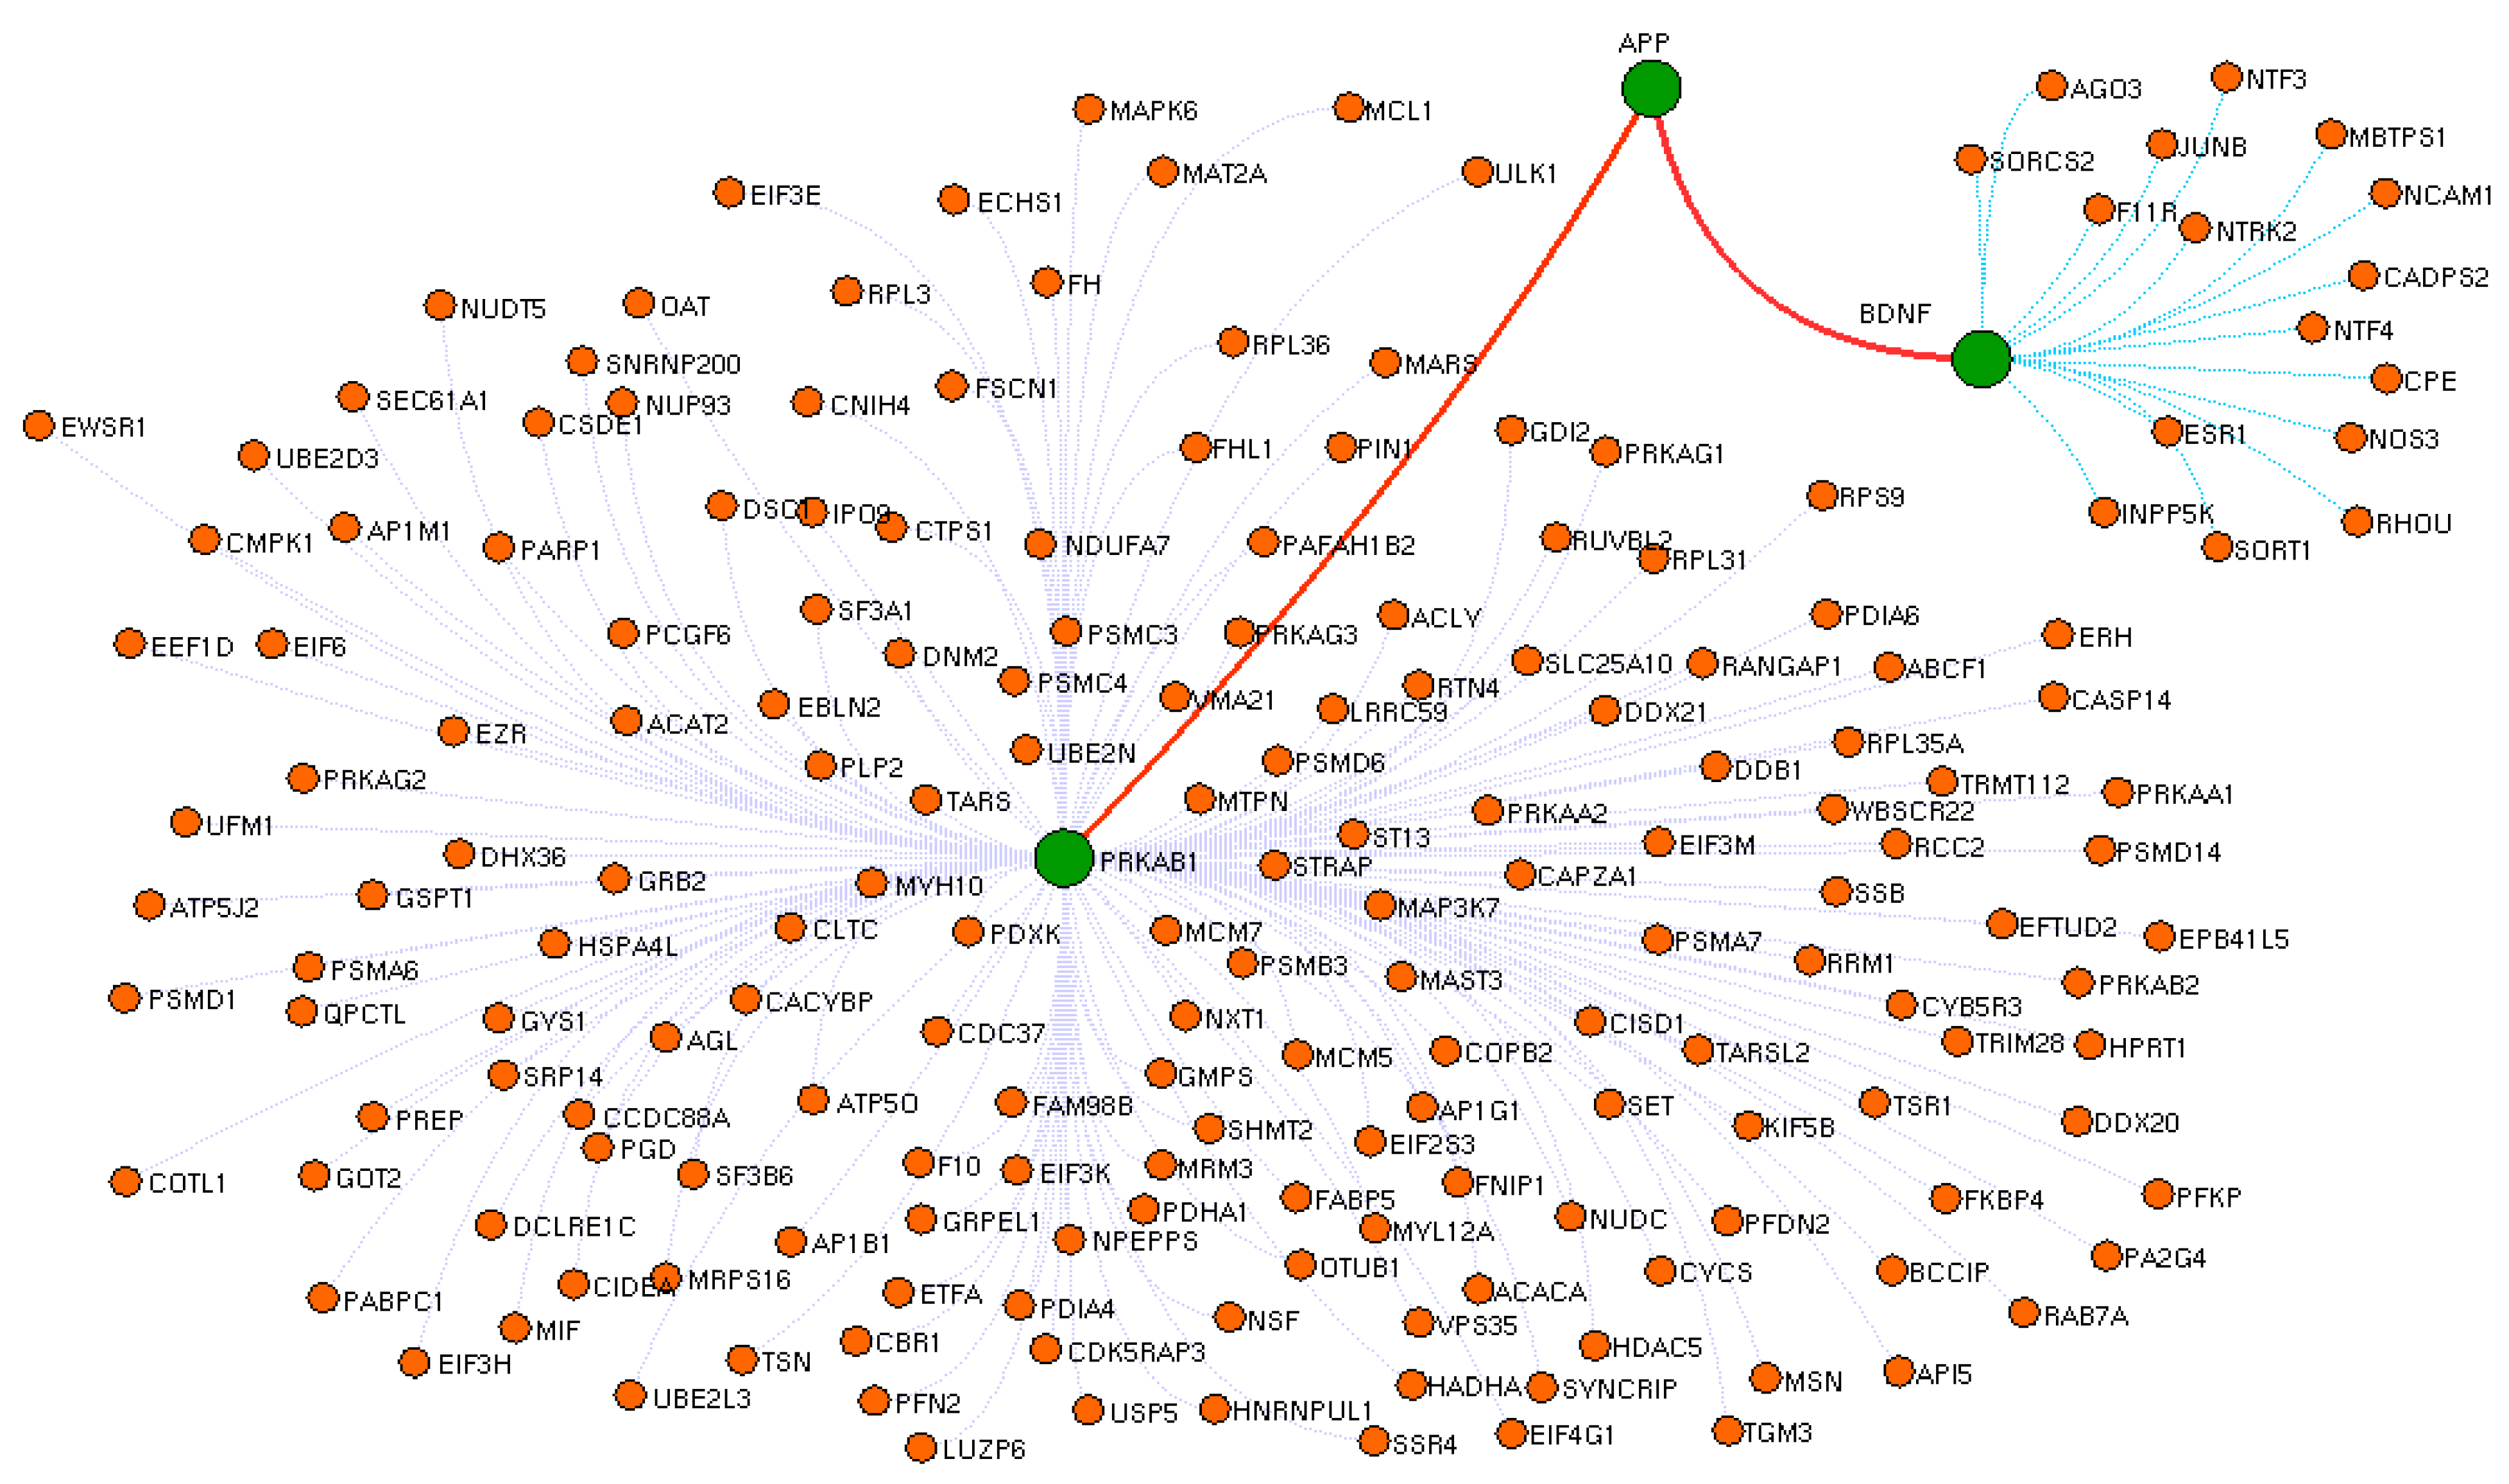

3.2. Drug Interactome Enrichment Analysis

3.3. Crucial Protein in Drug Interactome